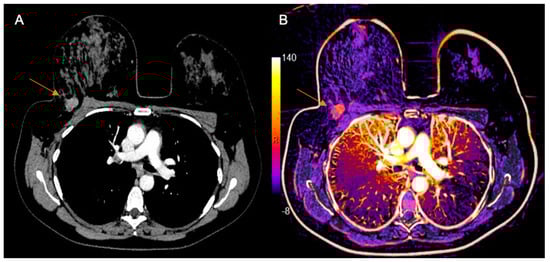

MDCT was performed with a specific protocol dedicated to breast evaluation, in prone position, using a specially made device (Figure 1), which reproduces the breast MRI coil. Exams were performed on a 160-slice MDCT scanner (Canon Aquilion Prime 160; Canon Medical Systems, Otawara, Japan), with a 0.5 mm slice thickness, before and after administration of 1–2 mL of the nonionic contrast material ioversol (Optiray 320; Mallinckrodt Medical Inc., St. Louis, MI, USA) per kilogram of body weight intravenously with a semiautomated power injector at a rate of 4 mL/s. The acquisition of chest images was performed 80–90 s after the contrast administration, which was previously reported as the optimal delay time to depict breast cancer [21]. Pre-contrast images were digitally subtracted from post-contrast images using a motion correction software (Sure Subtraction; Canon Medical Systems, Otawara, Japan) to improve the evaluation of enhancing lesions in the breast parenchyma and color-coded iodine maps were performed (Figure 2).

Figure 2. Example of chest MDCT with dedicated breast protocol. (A) Post-contrast axial image of chest MDCT in prone position showing a tumor in the right breast (arrow). (B) Subtracted imaging with color-coded iodine map showing the same tumor (arrow).